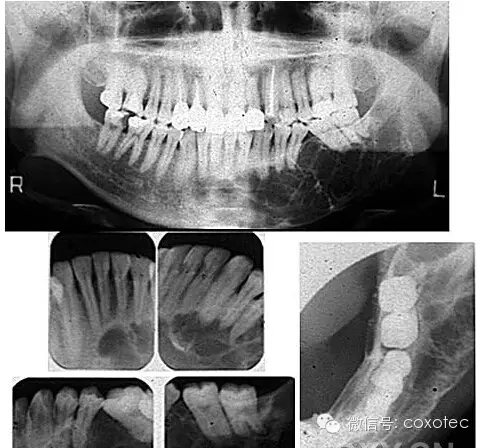

鎳鈦根管治療術(shù)是國(guó)際公認(rèn)現(xiàn)階段治療不可復(fù)性牙髓炎及根尖周?。ㄑ捞鄣闹饕颍┳顬閺氐缀童熜ё罴训囊环N方法,鎳鈦根管治療術(shù)通過清除根管內(nèi)的壞死物質(zhì),進(jìn)行適當(dāng)?shù)南?,充填根管,以去處根管?nèi)容物對(duì)根尖周圍組織的不良刺激,防止發(fā)生根尖周病變或促進(jìn)根尖周病變的愈合。

引進(jìn)根管治療儀是口腔內(nèi)科根管診療技術(shù)中的又一重大突破,鎳鈦合金材料引入牙科治療器械以來,得到了長(zhǎng)足發(fā)展。20世紀(jì)90年代歐美率先用機(jī)器代替手工驅(qū)動(dòng)鎳鈦擴(kuò)大系統(tǒng)完成根管擴(kuò)大。醫(yī)生習(xí)慣將之稱為“機(jī)擴(kuò)”。所具有的預(yù)備速度和質(zhì)量相較于傳統(tǒng)根管治療效率更高,效果更好,成形更好。并能最大限度的保存患者的牙齒,真正做到了事半功倍的神奇療效?,F(xiàn)代鎳鈦根管治療術(shù)把根管治療的水平提高到了一個(gè)新的臺(tái)階,并開辟了牙髓病根尖周病等疾病治療的廣泛前景。